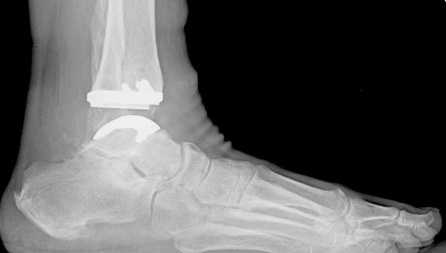

Эндопротезирование при артрите голеностопного сустава

Эндопротезирование — оптимальный метод хирургического лечения тяжелых повреждений голеностопного сустава. В отличие от артродеза, который предусматривает полное обездвиживание ГС, установка эндопротеза позволяет сохранить его функции. После операции человек получает возможность свободно ходить и вести привычный ему образ жизни. В то время как после артродеза у многих пациентов нарушается подвижность конечности и даже появляется хромота.

Эндопротез голеностопа на рентгене.

В ходе эндопротезирования врачи удаляют разрушенный сустав и на его место устанавливают искусственный протез. А при артродезе голеностоп обездвиживают, закрепляя кости в фиксированном положении при помощи металлоконструкций или аппарата Илизарова с целью внеочагового остеосинтеза.

Показания к эндопротезированию ГС: